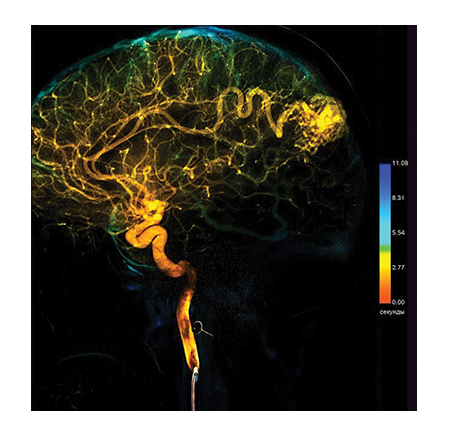

A special value of the angiography system consists in high information content of the obtained image. A unique imaging system based on a flat panel detector with spatial resolution of 50 μm, which is superior to foreign analogs regarding its specifications, ensures high diagnostic imaging quality. The examinations allow not only to obtain information about the functional state of the vessels and reveal the signs of disorders but also help determine the accurate localization and seriousness of the revealed abnormality using special calculation packages.

• Perfusion subtraction angiography for brain perfusion analysis